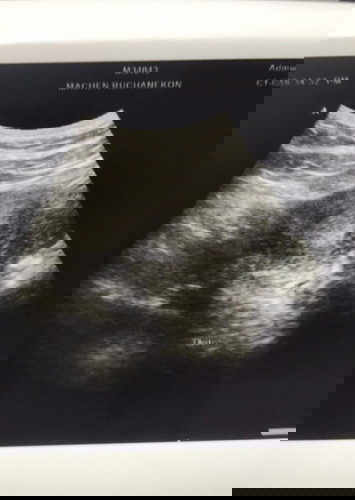

ขอสอบถามหน่อยค่ะ #ขอคำแนะนำหน่อยค่ะ พอดีสงสัยว่าตั้งครรภ์อยู่หรือป่าว แล้ววันนี้ไปพบหมอมาเพื่ออัลตร้าซาวด์ พบว่าเยื่อบุมดลูกหนาตัวประมาณ 4 ซม.ค่ะ #ใครมีประสบการณ์ ประจำเดือนขาดประมาณ 2 เดือนค่ะ ตรวจแล้วไม่ขึ้น 2 ขีด ไม่ทราบว่าเกิดจากอะไรค่ะ #ขอบคุณสำหรับคำตอบค่ะ